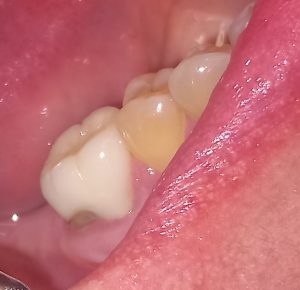

ΠΡΙΝ